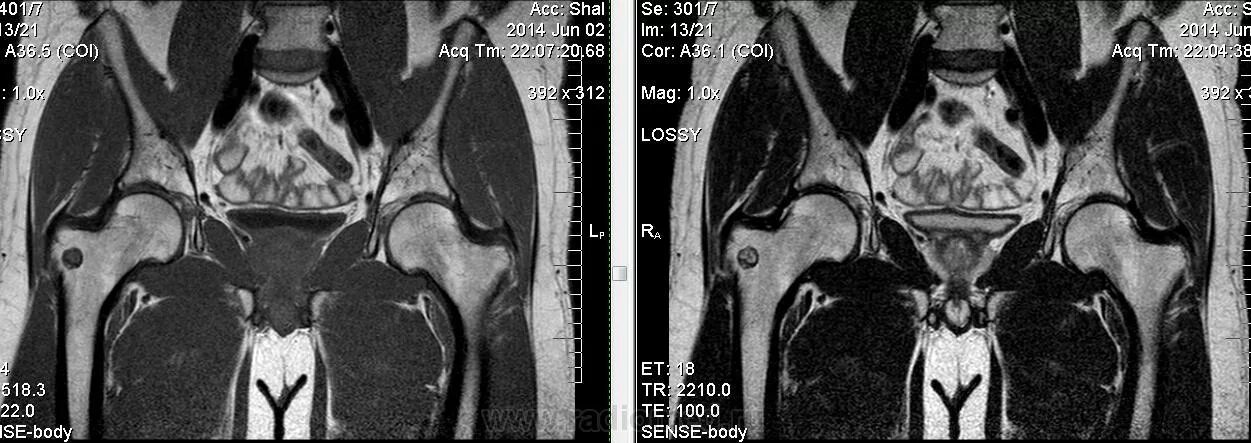

Остеома мрт